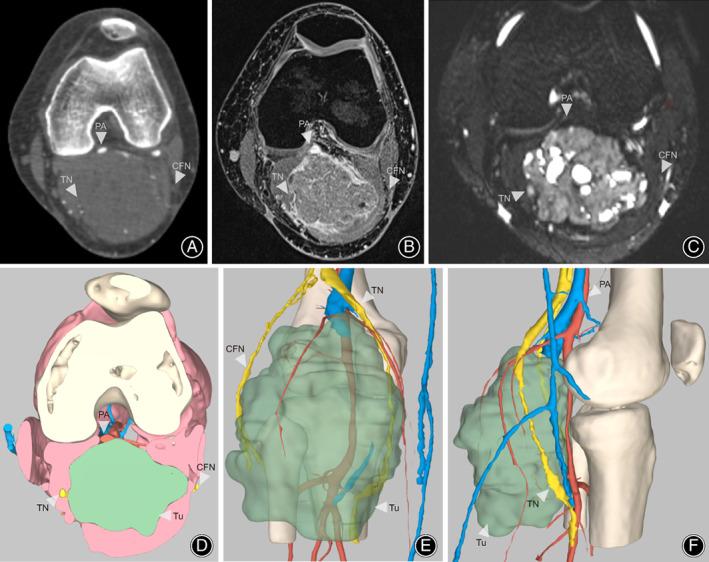

Personalized Surgical Planning for Soft Tissue Sarcoma of the Popliteal Fossa with a Novel 3D Imaging Technique.

Soft tissue sarcomas (STSs) arising from the popliteal fossa pose surgical challenges due to their proximity to critical neurovascular structures. This study aimed to investigate whether a novel 3D imaging technique highlighting these key anatomical structures could facilitate preoperative planning and improve surgical outcomes in STS.

This was a prospective, observational, pilot study. Between November 2019 and December 2020, 27 patients with STS of the popliteal fossa undergoing limb-sparing procedures were enrolled and assigned to either a control or intervention group. Control patients underwent traditional preoperative planning with separate computed tomography angiography, magnetic resonance imaging, and magnetic resonance hydrography. In the intervention group, 3D images were generated from these images, the tumor and skeletomuscular and neurovascular structures were revealed in three dimensions, and this was visualized on the surgeon's smartphone or computer. Primary endpoints were surgical margins and complications. Secondary endpoints included operative time, blood loss, serum C-reactive protein and interleukin-6, length of in-hospital stay, and limb function. Comparisons between groups were made using independent-sample t-tests for continuous data and the Mann-Whitney U and Fisher's exact tests for categorical data.